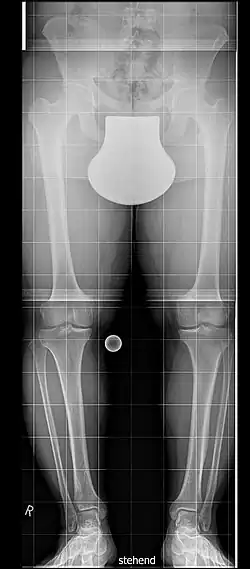

Bei Menschen mit Hypochondroplasie sind die Arme und Beine im Verhältnis zum Rumpf verkürzt. Dies ist jedoch weitaus weniger auffällig als bei der Achondroplasie. Auch ansonsten ähneln die Symptome denen der Achondroplasie, sind aber milder ausgeprägt. Häufig besteht eine Hyperlordose und eine Beinfehlstellung (meist O-Beine). Die Hände sind meist breit mit kurzen Fingern. In vielen Fällen ist der Ellenbogen nicht ganz streckbar, wohingegen aber die Knie und Handgelenke überstreckt werden können. Bei Kindern in den ersten Lebensjahren besteht meist eine leichte Muskelhypotonie, die üblicherweise aber keine große Rolle für die motorische Entwicklung spielt.[3]

Im Rahmen der Diagnostik werden meist zuerst andere Ursachen des Kleinwuchses durch Blutuntersuchungen ausgeschlossen, außerdem wird die linke Hand geröntgt, um das Knochenalter zu bestimmen.[7] Die Diagnose Hypochondroplasie wird dann aufgrund des Wachstumsverlaufes und eventueller weiterer Röntgenaufnahmen der Beine und der Wirbelsäule gestellt; oft erfolgt auch eine Analyse des FGFR3-Gens.